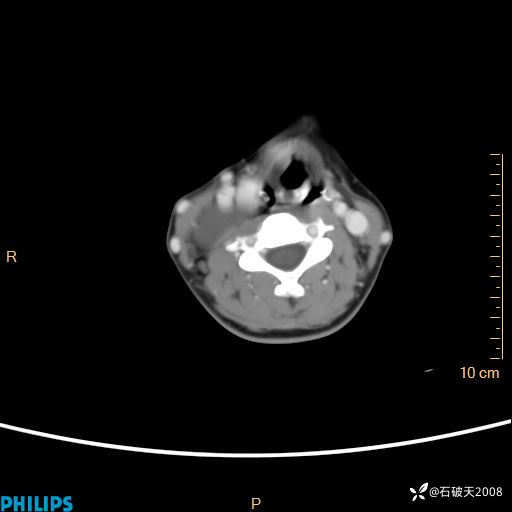

影像诊断要密切结合临床,真的很有必要(病理已公布)

女 21岁 主 诉:发现右侧颈部肿物18年余。

现病史:18年余前患者无明显诱因发现颈部偏右侧有一肿物,具体大小不明确,咳嗽、憋气时肿物增大,局部无疼痛,无吞咽不适,无胸闷及呼吸困难,至当地医院检查考虑良性病变(具体不详)并未做特殊处理,现患者自觉肿物随年龄增长而进一步变大,今日至我院行颈部CT平扫+增强提示:1.右侧颈根部、锁骨上窝及纵隔内异常密度影,考虑良性病变,淋巴管瘤?囊肿?请结合临床。2.双侧颈部小淋巴结。建议结合临床及其他相关检查。现为行进一步治疗,门诊以“颈部局部肿物”为诊断收住我科,发病来患者神志清,精神可,饮食睡眠可,大小便正常,体重无下降。

动脉期